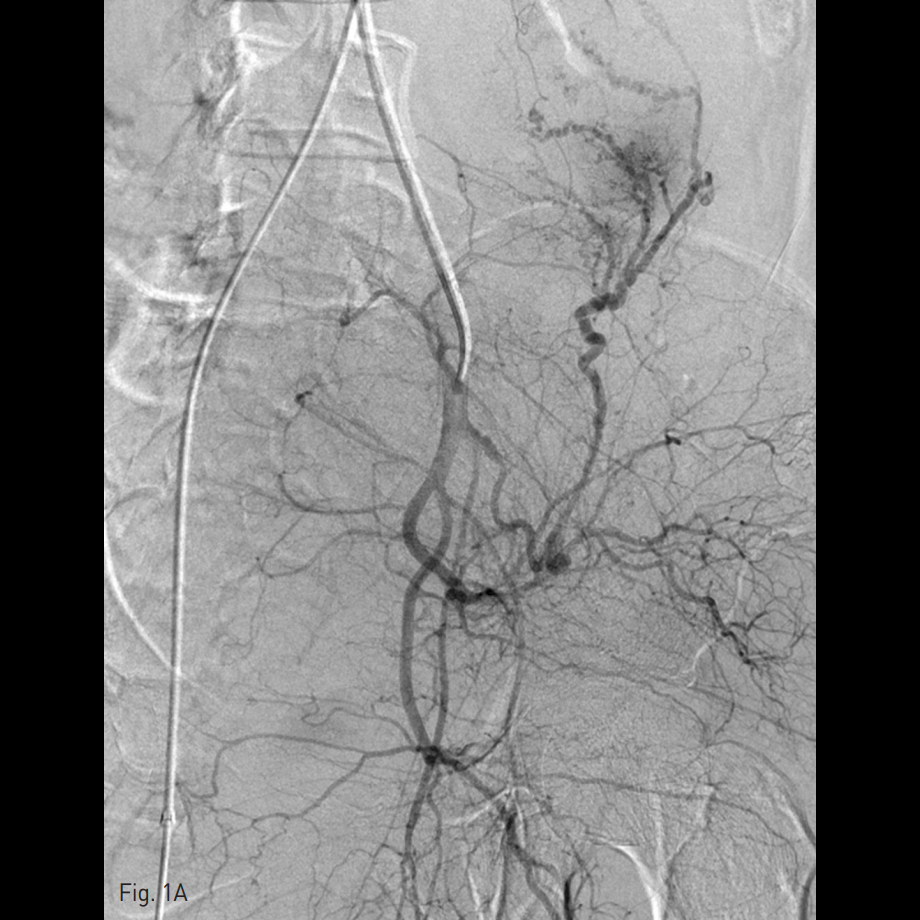

우측 총대퇴동맥을 천자하여 5 Fr sheath를 삽입하고, 5 Fr RUC catheter (Roberts Uterine Catheter, COOK medical, Bloomington, IN, USA)를 이용하여 좌측 내측 장골동맥을 선택하여 조영술을 시행한 뒤 좌측 자궁동맥을 선택하여 조영술 시행하였으며 (Fig. 1A), 출혈의심소견이 있어 gelfoam을 이용하여 색전술을 시행하였다 (Fig. 1B). 이후에 시행한 우측 내측 장골동맥을 선택하여 조영술을 시행한 뒤 (Fig. 1C), 우측 자궁동맥을 초선택하여 조영술을 시행하였을 때, 우측 자궁동맥이 비후되어 있어, gelfoam을 이용하여 색전술을 시행하였다. 색전술 직후 산부인과 진찰에서 지속적인 출혈소견이 보였다. 이에 5 Fr pigtail catheter를 이용하여, 대동맥 조영술을 시행하였다. 하장간막동맥 (Inferior mesenteric artery)으로 부터 출혈 소견이 관찰되었다 (Fig. 2A). 이에 대해서 2.2 Fr 마이크로카테터 (Progreat, Terumo, Japan)를 이용하여 하장간막동맥을 초선택하여 코일(Nester microcoil, COOK Medical, Bloomington, IN, USA)과 gelfoam (Spongostan, Ferrosan Medical Devices, Denmark)을 이용하여 색전술을 시행하였다 (Fig. 2B). 이후 다시 하장간막동맥 조영술을 시행하여 더 이상의 출혈이 없음을 확인하고 시술을 종료하였다 (Fig. 2C).

Fig. 1

D. Right uterine artery was complete embolization with gelfoam sponge.